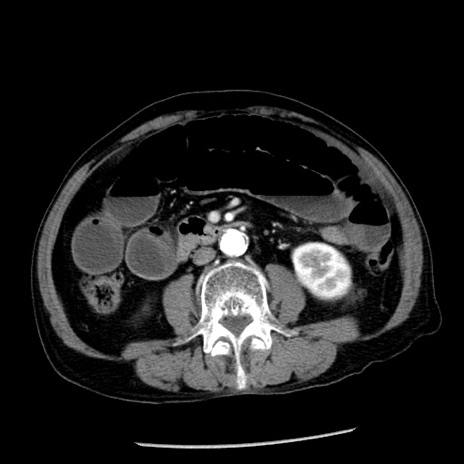

症例26(横断像)

【症例】80歳代男性

【主訴】嘔吐

【現病歴】昨晩2回嘔吐あり、今朝になっても嘔吐あり。来院。

【既往歴】胃潰瘍

【身体所見】意識清明、BT 37.6℃、BP 166/95mmHg、HR 100bpm、SpO2 97%、腹部:平坦・軟、腸蠕動音聴取良好、圧痛なし。

【データ】WBC 21900、CRP 1.46